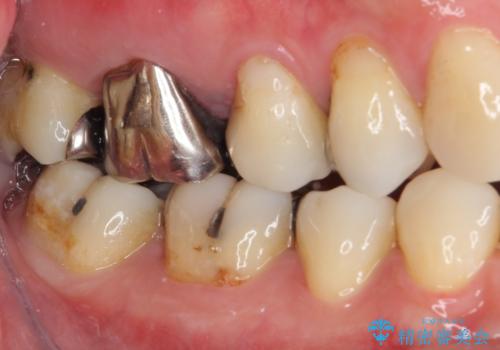

- 上の奥歯に咬んだときの痛みを感じて来院された患者様です。

まずは根管治療を行い、その後フルジルコニアクラウンにて補綴することとしました。

根管治療後には痛みが引き、半年後のレントゲンからは根尖部の病変が縮小している様子が分かりました。

咬んだときの感触も良好で、患者様には大変満足していただきました。